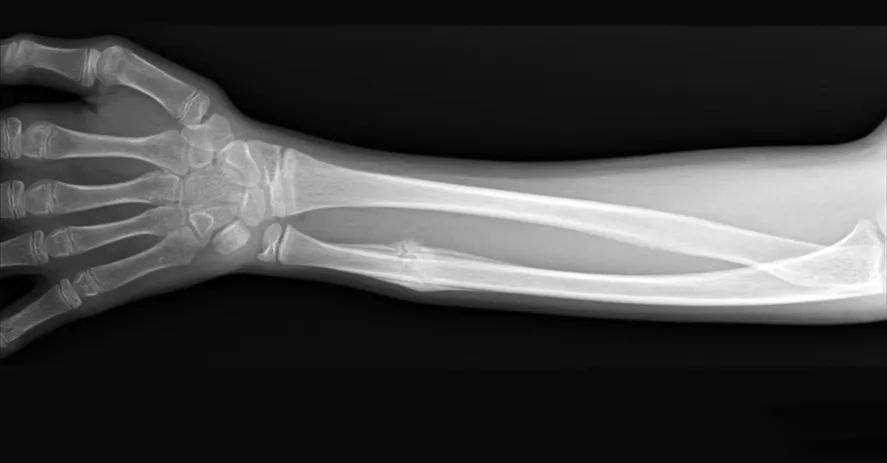

X 线片上并无明显的外骨痂形成,骨折线逐渐消失,其特征为愈合过程中无骨皮质区吸收,坏死骨在被吸收的同时由新的板层骨取代,达到皮质骨间的直接愈合。